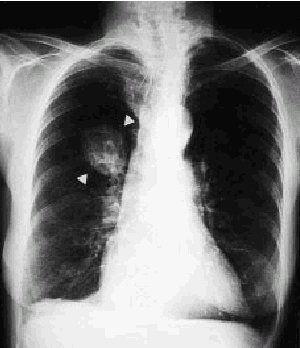

Fig. 2.

Mujer de 72 años que presenta como único antecedente personal de interés una tuberculosis pulmonar en la infancia. Refiere un cuadro clínico que tras ser minuciosamente estudiado es diagnosticado como neoplasia de colon izquierdo, decidiéndose realizar una hemicolectomía izquierda. En la radiografía preoperatoria de tórax se encuentra una masa en el lóbulo pulmonar superior derecho, de contornos bien definidos y sin calcificaciones (fig. 1). Ante la sospecha diagnóstica de una posible metástasis pulmonar se decide realizar una tomografía computarizada (TC) de tórax. En ella se visualiza una masa en el lóbulo pulmonar superior derecho, de contornos bien definidos y de un diámetro máximo de 4 cm, en cuyo interior se observan áreas de densidad partes blandas y múltiples áreas reticuladas hipodensas que muestran densidad correspondiente a grasa (fig. 2). Ante estos datos puede establecerse con fiabilidad el diagnóstico por TC de hamartoma pulmonar gigante. Tras su resección por minitoracotomía se confirma anatomopatológicamente que se trata de un hamartoma pulmonar de predominio condroide.